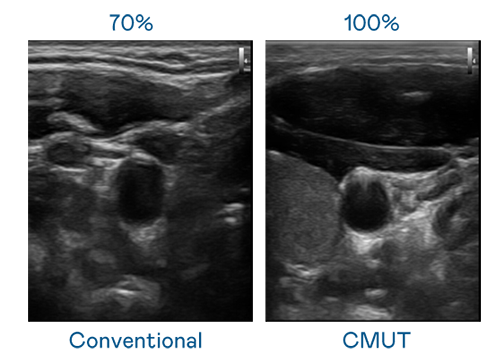

CMUT 技术是一种用电容式微机电元件来产生超音波讯号的技术。与传统 PZT 压电式技术相比,CMUT 频宽增加 30%,更宽频的超音波讯号让影像解析度大幅提升,是实现高影像品质医疗超音波扫描、促进精准医疗发展的关键技术。

超音波影像的解析度高低,首先取决于探头能发出的讯号频宽。尊龙时凯人生就是搏官网 CMUT 可提供高清晰的超音波讯号,提供高频宽、高灵敏度、影像纹理细节更高的超音波影像,协助医护人员缩短影像判读时间及利用精准的医疗影像进行诊断。